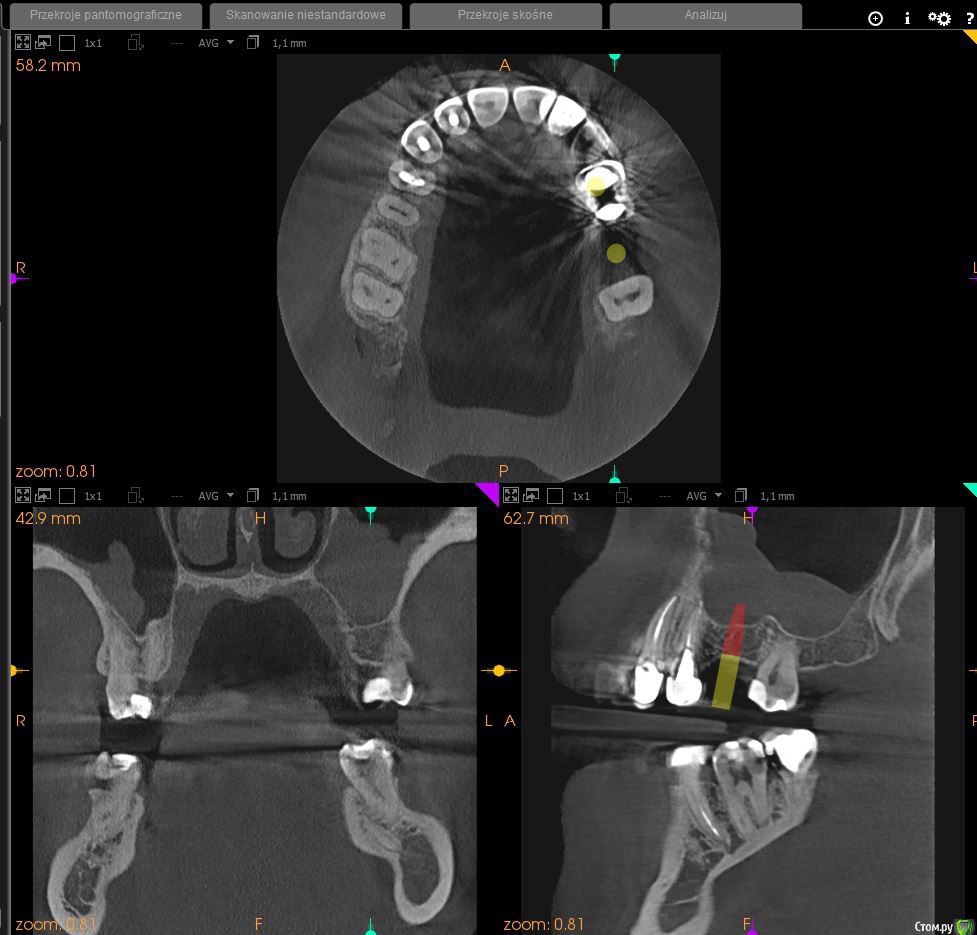

Desade Опубликовано 17 мая, 2020 Поделиться Опубликовано 17 мая, 2020 Добрый день, меня зовут Юрий, мне 32 года. Я живу в Пoльше. Сразу извините за возможную неправильную терминологию. В среду мне поставили два импланта на 4 и 6е место верхней челюсти. шестого зуба у меня не было, четвертый вырывали, так как там был какой-то процесс возле корня. На одном из отверстий поднимали дно пазухи и подсыпали штучную кость + мою с нижней челюсти. Плюс еще латали дыру в кости, из которой виднелся корешок. Процесс длился часа три. Проблема в том, что уже прошло 5 дней после операции, а чувствительность части верхней губы до конца не восстановилась. Скажите пожалуйста, что могло пойти не так? На счет остального, то никаких выделений во рту нет, сильной боли нет, только дискомфорт, вроде как все заживает. Опухлость имеется. Может он как-то придавил нерв? Очень неприятные ощущения от постоянного онемения, и будет ужасно, если они останутся на всю жизнь.. Доктор прописал принимать неделю Аугументин 2 табл/день, Метронидазол 5 дней 3 табл/день. И дексаметазон 5 дней. Прикрепил скриншот панорамы до операции, и по ссылке загрузил весь файл панорамы. https://dropmefiles.com/e0EqVТак же есть фото процесса. Спасибо! Ссылка на комментарий